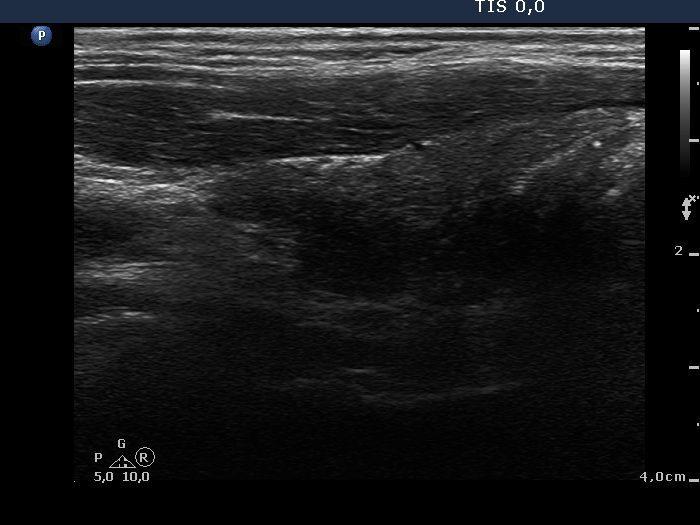

Ultrasonography: The size of the thyroid decreased dramatically and became atrophic. The right lobe still presented a small deeply hypoechogenic area. In contrast with the first examination, the basic echo structure of the left lobe was not normal but moderately hypoechogenic. The vascularization was decreased and average, right and left lobe, respectively.

Second examination 14 months after the initial (4th row of images):